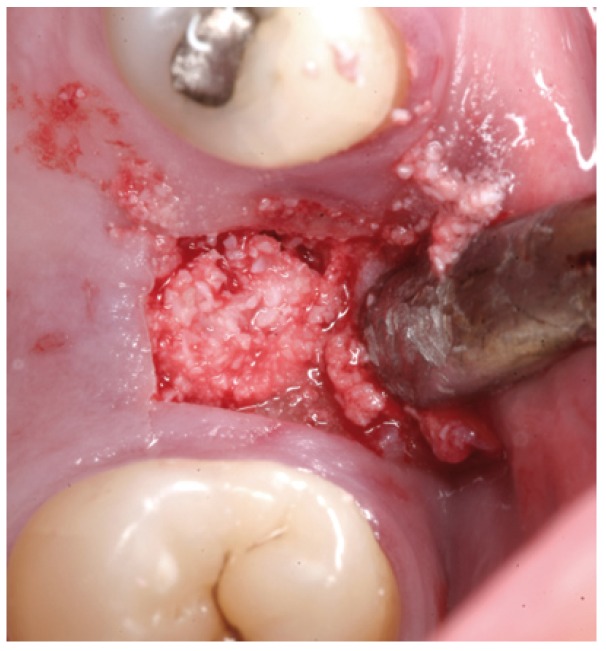

Osteotomy preparation using the drill with stopper attached

The hydraulic system is seen in action attached to the osteotomy, the tubing, and the syringe